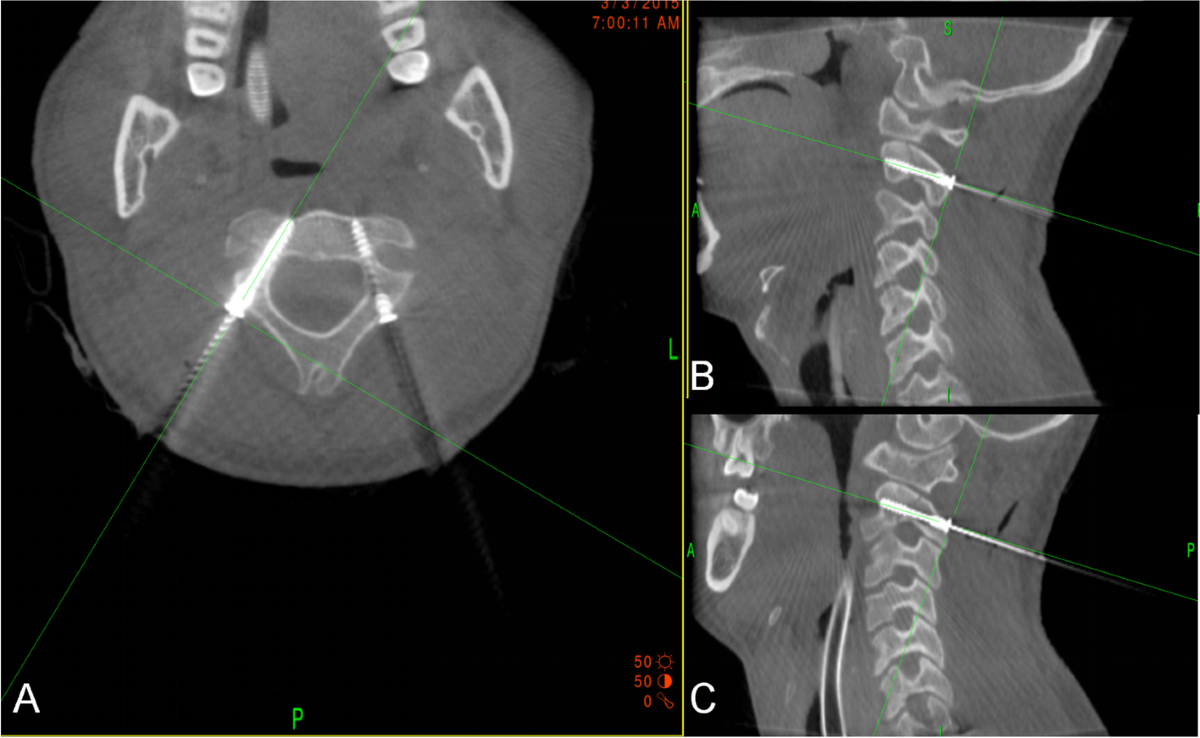

Minimally invasive percutaneous new designed transpedicular lag-screw  fixation for the management of Hangman fracture using O-arm-based  navigation: a clinical study | BMC Musculoskeletal Disorders, image size:1047x835

Minimally invasive percutaneous new designed transpedicular lag-screw fixation for the management of Hangman fracture using O-arm-based navigation: a clinical study | BMC Musculoskeletal Disorders